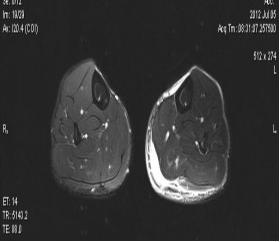

典型病例:患者,男,40岁,体能训练致左小腿肌肉撕裂伤并巨大血肿,给予脉冲磁疗、中频电疗和下肢肌肉训练指导后,血肿逐渐消退,两个月后肌肉恢复正常,继续参加训练。